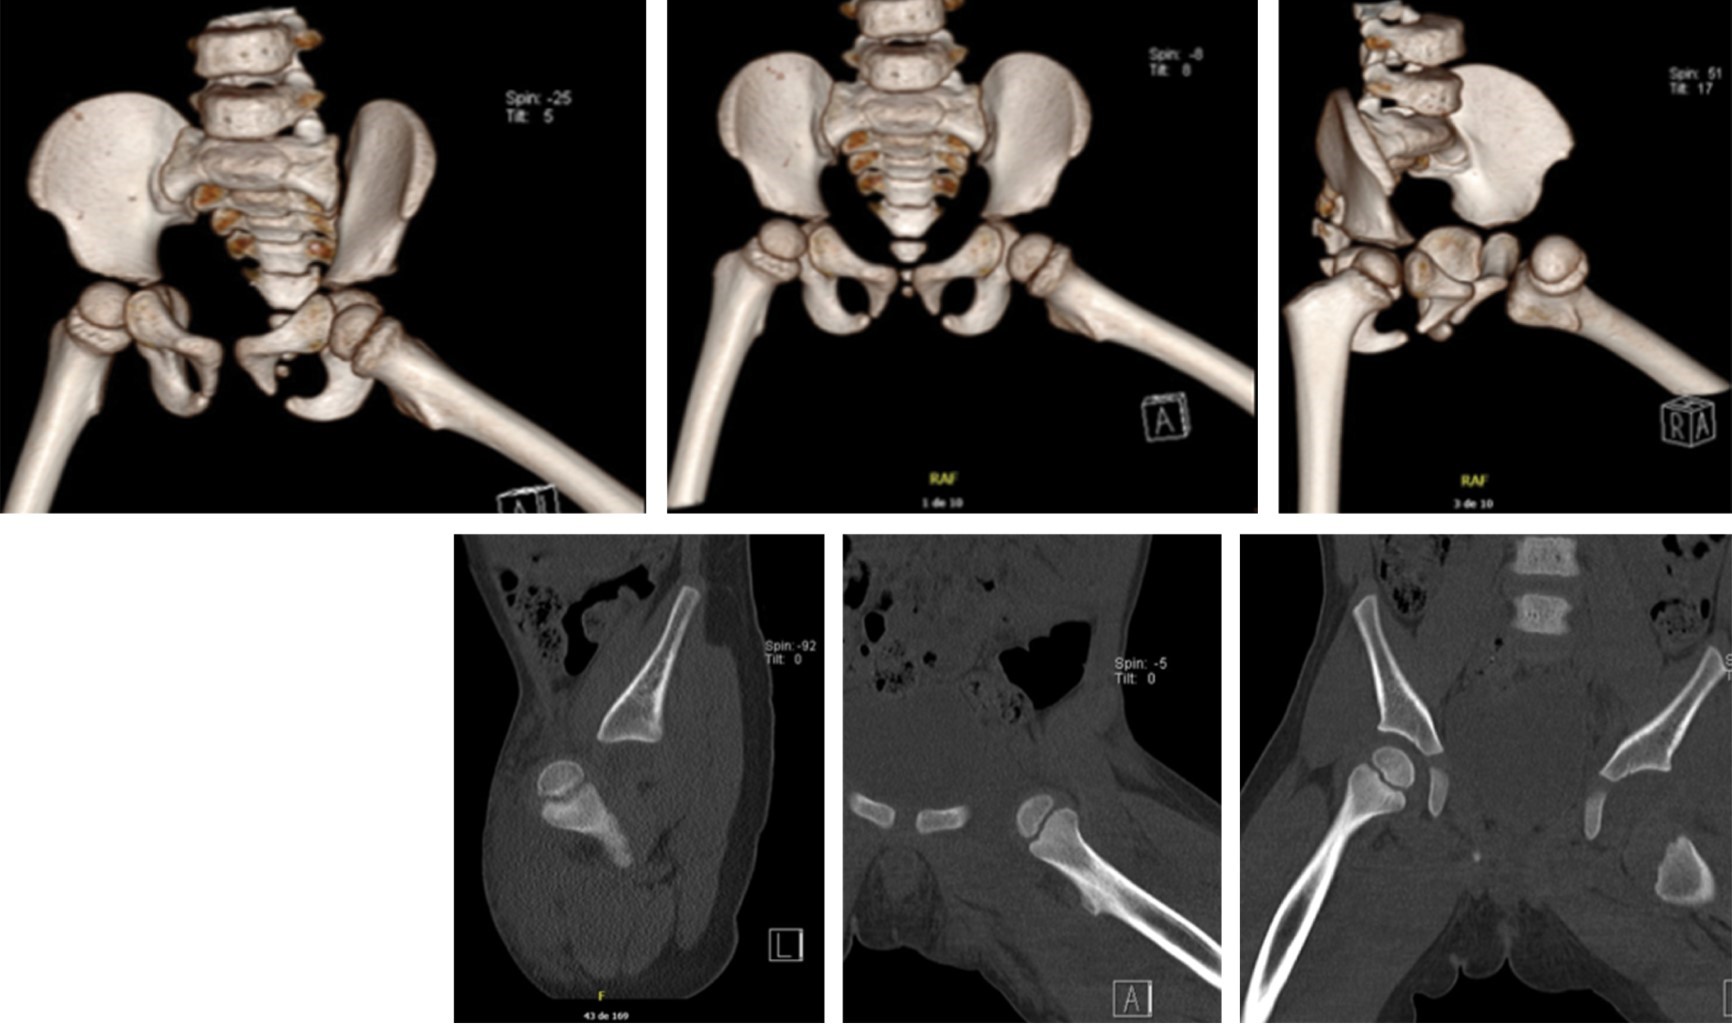

Traumatic anterior hip dislocation in children: a case report

Traumatic anterior dislocation of the hip is uncommon in children, and may result from low energy trauma. Treatment, like all traumatic dislocations, is an emergency. We present the case of a two-year-old boy with traumatic anterior hip dislocation following a fall. Importance: There is little support in the literature for traumatic anterior dislocation of the hip in children due to low energy trauma.

Figure 1

Figure 2

Figure 3